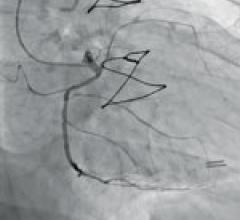

Canon Medical Systems’ offering includes: computed tomography, magnetic resonance, ultrasound, X-ray, cath and EP labs.